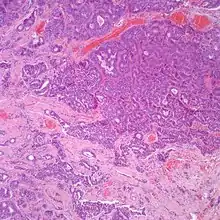

A hematoxylin and eosin stained intermediate power showing an infiltrating tumor with glandular and neuroendocrine features in a neuroendocrine adenoma of the middle ear.

At the time of surgery, the tumor tends to peel away from the adjacent bones, although not the ossicles. It is usually fragmented, soft, rubbery and white to gray-tan. Due to the anatomic confines of the region, tumors are usually <1 cm.[8] The tumors arise below the surface, are unencapsulated, and have an infiltrative pattern of growth, composed of many different patterns (glandular, trabecular, cords, festoons, single cells). The tumor shows duct-like structures with inner luminal, flattened cells and outer, basal, cuboidal cells. The cells may have an eccentrically placed nucleus. The nuclear chromatin distribution is "salt-and-pepper", giving a delicate, fine appearance. Nucleoli are small with inconspicuous mitoses. There may be secretions in the gland tumor. It is possible to see a concurrent cholesteatoma.[2]